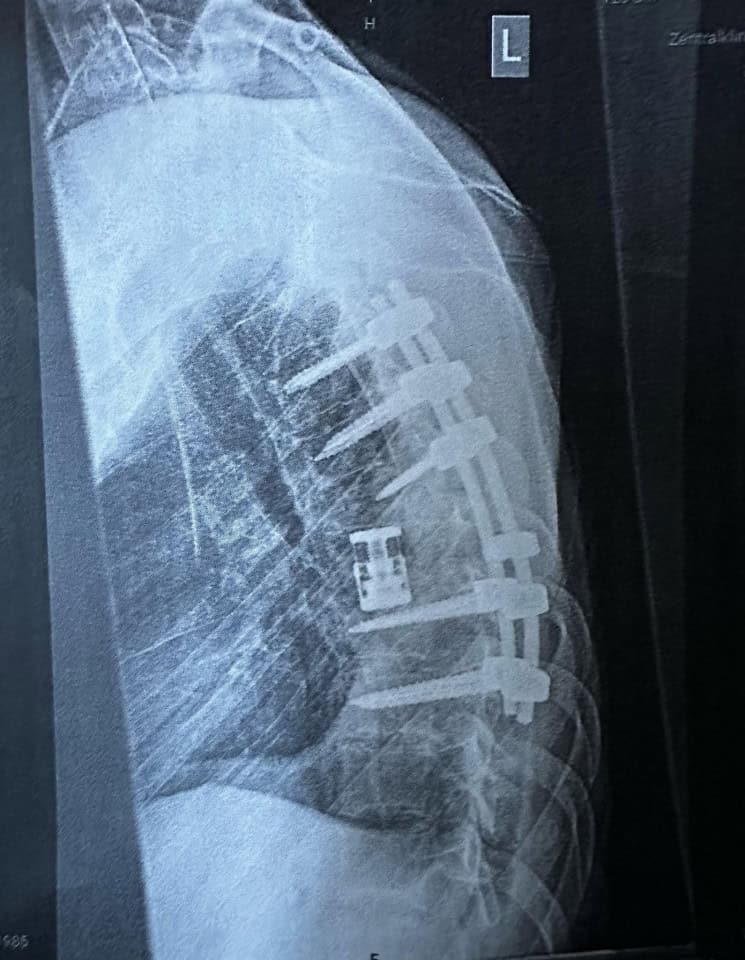

Noch am selben Tag wurde Kevin Wilkniß in die Uniklinik Leipzig gebracht und operiert. Der siebte Brustwirbel war gebrochen, mehrere Rippen ebenfalls. Zudem war die Lunge verletzt, was eine weitere Operation verzögerte. „Die erste OP war nur das Nötigste, sie mussten abbrechen, weil mein Kreislauf kollabiert ist.“ Erst später, in einer Spezialklinik für Querschnittslähmung, konnte der beschädigte Wirbel ersetzt und der Rücken stabilisiert werden – durch mehrere riskante Eingriffe.